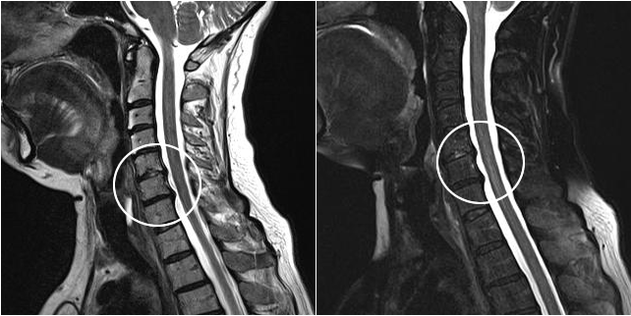

Modern diagnostic methods include MRI and CT, which make it possible to accurately examine the process of destruction of cartilage and bone tissue.Also, using this technique it is easy to diagnose hernias and other soft tissue defects near the source of the disease.